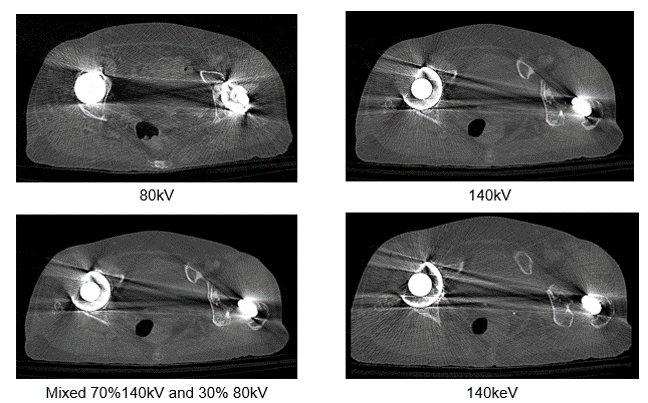

It is also possible to adapt the kV values used based on the visualized structure or to use dual-energy protocols. Notice the difference in streaking in these three images.

Let’s look at the differences in these four images taken at different dual energy levels. Compare the streak artifacts with the 80kV, 140 kV, the mixed acquisition of 140kV and 80 kV and the last at 140 keV.